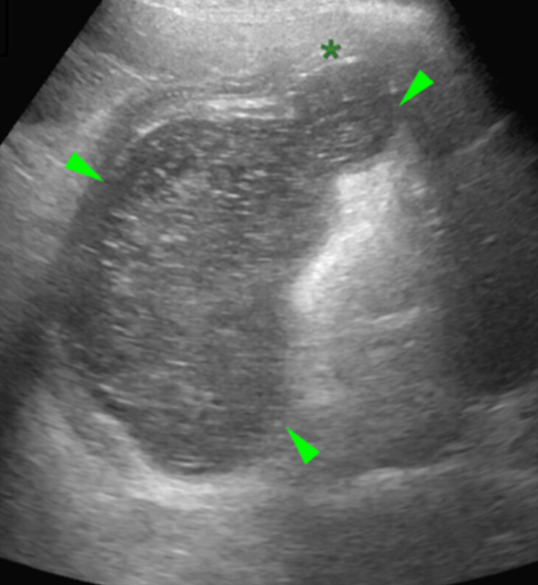

반려견의 위벽내 농양

이번 증례는 위벽에서 발생한 농양 증례이다.

두꺼워졌고, 층간 구조가 잘 안 보이니 종양?이라고 생각하면 안 된다는 의미가 될 것이다.

당연히 FNA를 해보아야 한다.

다발성으로 발생한 게 눈에 띈다.

감별진단에서 꼭 빼지 말고 생각해 보아야 할 것이다.